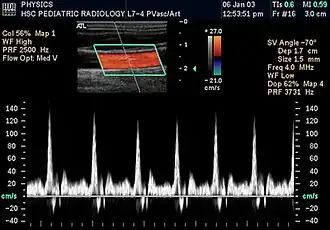

Duplex ultrasonography sometimes refers to Doppler ultrasonography or spectral Doppler ultrasonography.[3] Doppler ultrasonography consists of two components: brightness mode (B-mode) showing anatomy of the organs, and Doppler mode (showing blood flow) superimposed on the B-mode. Meanwhile, spectral Doppler ultrasonography consists of three components: B-mode, Doppler mode, and spectral waveform displayed at the lower half of the image. Therefore, "duplex ultrasonography" is a misnomer for spectral Doppler ultrasonography, and more exact name should be "triplex ultrasonography".[3]

Colour Doppler shows the direction of the blood flow in red or blue (either towards or away from the transducer). Meanwhile, spectral Doppler not only shows the direction of blood flow, it also shows the phases (pulsatility) and acceleration of the blood flow. Any sudden changes in direction of blood flow produces audible sounds on the ultrasound machine.[3]

In spectral Doppler, the y-axis shows the direction and velocity of the flow. Meanwhile, the x-axis (as known as "baseline") shows the flow over time. The gradient at any point on the waveform would therefore shows the acceleration of the flow. In "antegrade" flow, the blood flows according to the normal flow within the circulatory system (e.g. veins flow towards the heart while arteries flows away from the heart). In "retrograde" flow, the flow would reverse (e.g. veins flow away from heart or arteries flow towards the heart). However, "retrograde" flow can be both abnormal or normal. For example, in portal hypertension, there is an abnormal portal venous flow where it flows away from the liver (hepatofugal flow) instead of the normal flow towards liver (hepatopetal flow). In jugular venous pressure waveform of the internal jugular vein, the retrograde "a" waveform is a normal flow due to right atrium contraction. Both antegrade or retrograde flow can be either towards or away from the probe transducer, depending on the position of the probe relative to the blood flow. Blood flow toward the transducer would appear above the baseline while blood flows away from the transducer will appear below the baseline. Waveform of the flow can be classified as: pulsatile (as in arteries), phasic (as in veins), non-phasic (as in diseased veins), and aphasic (no flow). Spectral broadening (thickness of the waveform) increases from large vessels (plug flow) to medium vessels (laminar flow) to small/stenotic/diseased vessels (turbulent flow) due to a larger variety of blood with different ranges of velocities in those with turbulent flow.[3]